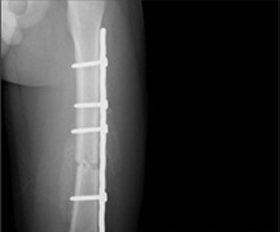

대퇴골 원위부 골절 >

금속판 1개 : 12~18개월

금속판 2개 : 18개월 이후 6월 간격

단계적 제거

골수정 : 24~36개월